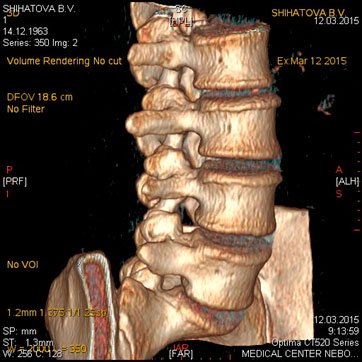

МСКТ позвоночника и спинного мозга.

Метод МСКТ очень ценен для выявления дегенеративно-дистрофических изменений, диагностируются грыжи дисков и элементы, суживающие позвоночный канал. МРТ превосходит визуализацию спинного мозга, содержимое дурального мешка, возможность увидеть другие уровни. Однако для пациентов с типичным течением болезни локализацией симптомов на одном уровне с одной стороны МСКТ обычно достаточна для постановки диагноза.

Показания:

- подозрение на опухолевое, метастатическое поражение с деструкцией

- травматическое поражение

- подозрение на грыжу диска (с обязательным указанием сегмента поражения) при невозможности проведения МРТ

- воспалительные процессы (специфические и неспецифические) с деструкцией костных структур

Подготовка: не требуется. Предварительное рекомендуемое обследование: заключение невролога